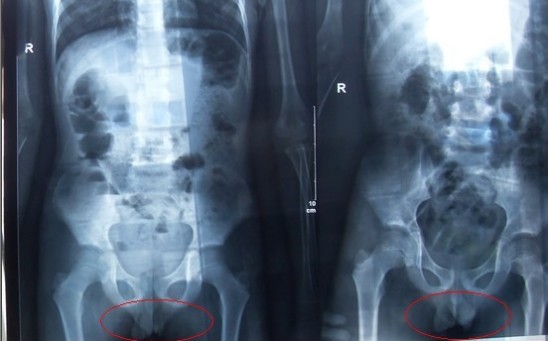

醫療X光機的拍攝方式和基本原理與長途汽車站的X射線行李安檢機,其實是一樣的,只是劑量的不同而已,但很多人估計會有疑問:X射線的輻射是否會對人體造成傷害,會不會影響正常的成長和發育? &nbs...